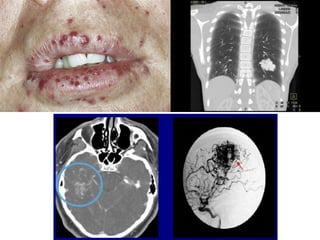

Rendu-Osler-Weber Syndrome

(Hereditary Hemorrhagic Telangiectasia)

• Uncommon disorder of systemic fibrovascular

dysplasia

– Telangiectasias

– Arteriovenous malformations

– Aneurysms of the skin, mucous membranes, viscera, and

CNS

• In childhood, diagnosed from the development of

multiple small red or purple angiomas

• Later enlarge and may cause recurrent epistaxis or GI

or GU hemorrhages

• Scattered angiomas in the brain or spinal cord

– Hemorrhage

– Seizures

– Localized cerebral or spinal dysfunction

• Subarachnoid hemorrhage (SAH) in

association with multiple arterio-venous

malformations, cutaneous telangiectasias,

repeated epistaxis or a family history of SAH

• Septic emboli to brain because of these

vascular defects in the lung

Rendu-Osler-Weber Syndrome (Hereditary HemorrhagicTelangiectasia) • Uncommon disorder of systemic fibrovascular dysplasia – Telangiectasias – Arteriovenous malformations – Aneurysms of the skin, mucous membranes, viscera, and CNS • In childhood, diagnosed from the development of multiple small red or purple angiomas • Later enlarge and may cause recurrent epistaxis or GI or GU hemorrhages • Scattered angiomas in the brain or spinal cord – Hemorrhage – Seizures – Localized cerebral or spinal dysfunction

• Subarachnoid hemorrhage(SAH) in association with multiple arterio-venous malformations, cutaneous telangiectasias, repeated epistaxis or a family history of SAH • Septic emboli to brain because of these vascular defects in the lung

• #72 This diagnosis should be excluded in all patients with subarachnoid hemorrhage (SAH) in association with multiple arterio-venous malformations, cutaneous telangiectasias, repeated epistaxis or a family history of SAH. Septic emboli that reach the brain because of these vascular defects in the lung are another manifestation of this disease that may present to the neurosurgeon as a brain abscess.

• #73 Telangiectasias Arteriovenous malformations Aneurysms of the skin, mucous membranes, viscera, and CNS